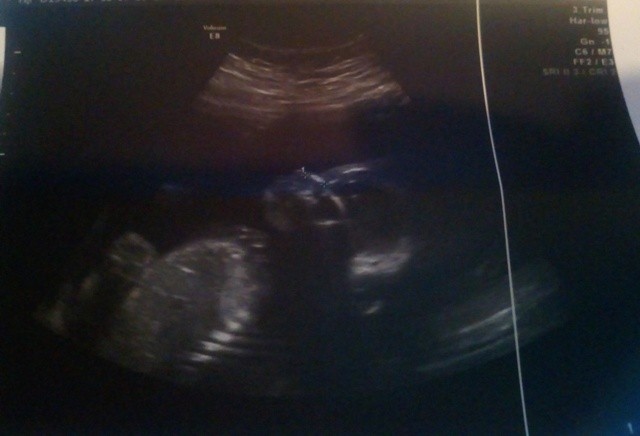

właśnie wróciliśmy z usg połówkowego.

19t1dzien

waga 280g +- 40g

wszystko ok, dzieciaczek rozwija się prawidłowo no i już na 100% dziewczynka

To i ja dołączę do do szczęśliwych mamuś noszących po serduszkiem zdrowe dziewczynkiwróciłam właśnie z połówkowych, 20+0, 350 g. Pięknie rozłożyła nóżki, ale buźki nie chciała pokazać. Ale i tak się strasznie cieszę <3